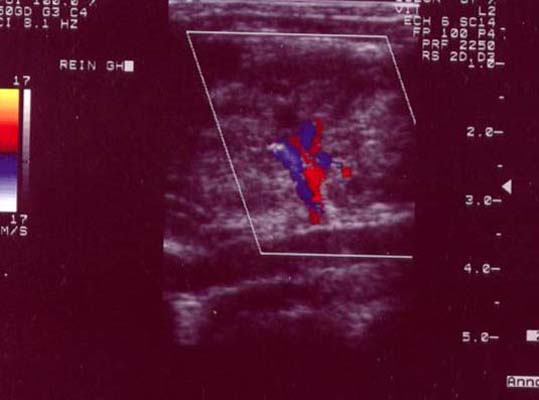

Thrombose veine rénale doppler